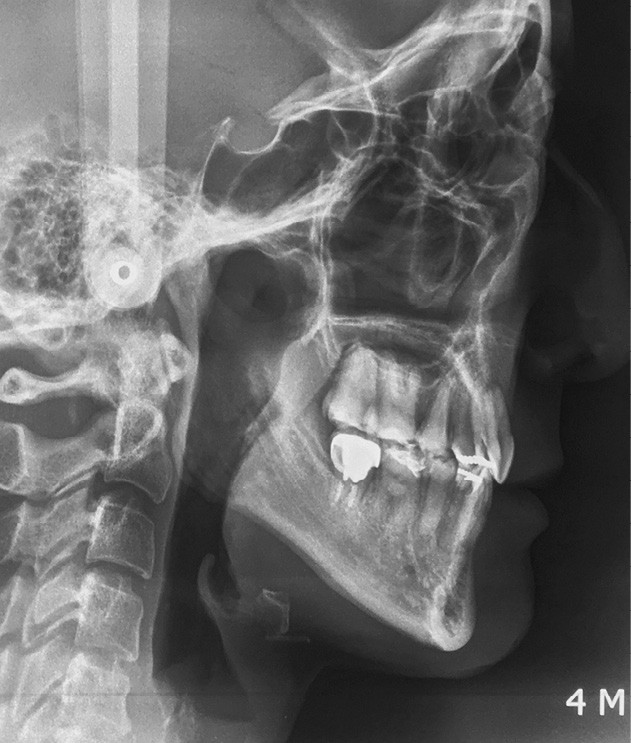

Sur le plan squelettique, on retrouve une classe III de Ballard par hypomaxillie, dans un schéma facial hyperdivergent.

Sur le plan dentaire, la patiente est en classe III droite et gauche, canine et molaire de 6 mm, avec une occlusion inversée antérieure localisée à 11, 12 et 22. Elle présente une dysharmonie dents-arcades sévère, une agénésie d’une incisive mandibulaire est à signaler, et les troisièmes molaires ont été extraites à l’âge de 21 ans.